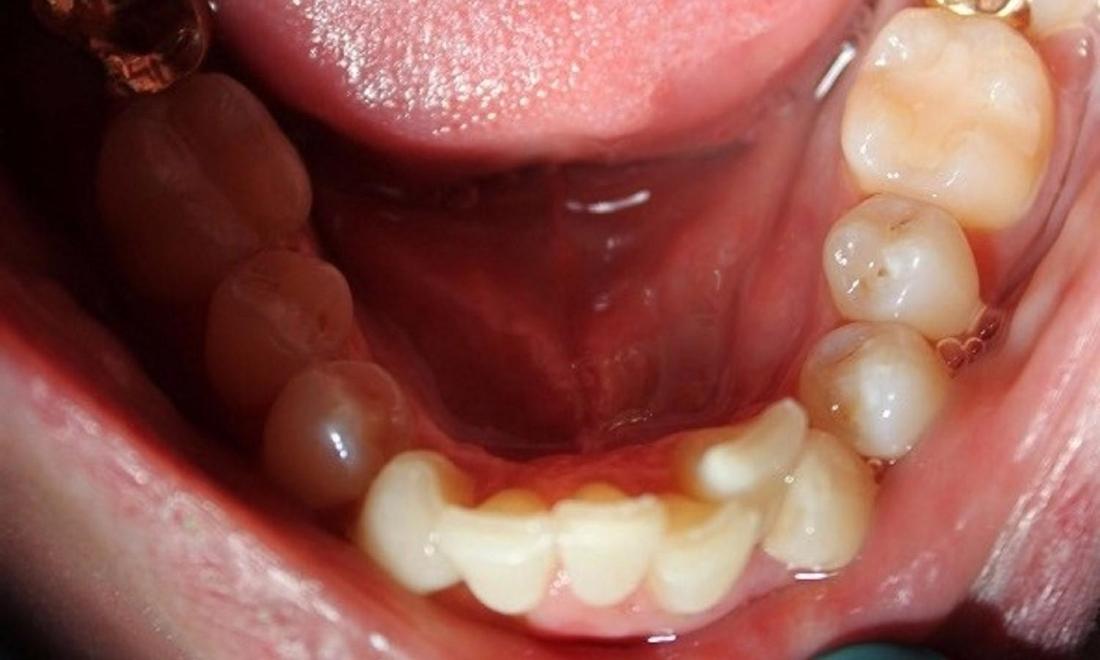

This patient's crowded teeth were posing a few different risks including plaque and tartar buildup which can harbor harmful periodontal bacteria, risk of periodontal disease, tooth, and bone loss. After two years of Invisalign treatment, teeth have aligned properly for a healthier mouth.

crowded lower teeth before an invisalign treatment | invisalign dentist in vienna va aligned lower teeth after an invisalign treatment | dentist invisalign vienna